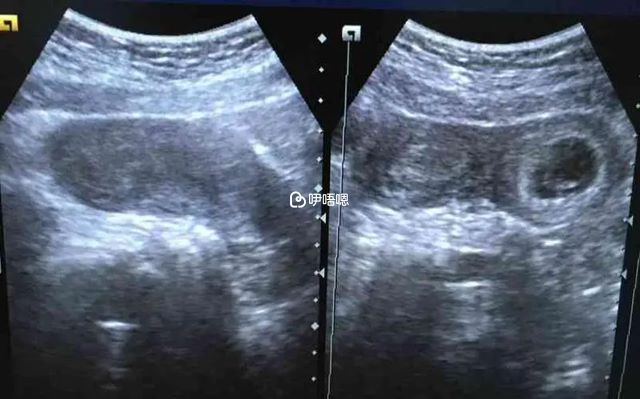

- 1. 超聲檢查:通過超聲檢查顯示出來的子宮縱隔聲像影象較為典型,就結果來看診斷並不困難,但需要注意的是雙角子宮比較類似,診斷時需仔細辨別。

一般來說從橫切面看,子宮橫徑較寬,在宮體中央會有明顯衰減的縱隔回聲,同時見兩個宮體顯影,從縱切面來看會見一宮體顯影消失後再出現一體回聲。 - 2. 碘油造影:碘油造影是子宮縱隔檢查中比較常見的診斷方法,但造影檢查的缺點在於不能區別雙角子宮與不完全縱隔子宮,還有雙子宮和完全縱隔子宮,只能診斷子宮是否有畸形。